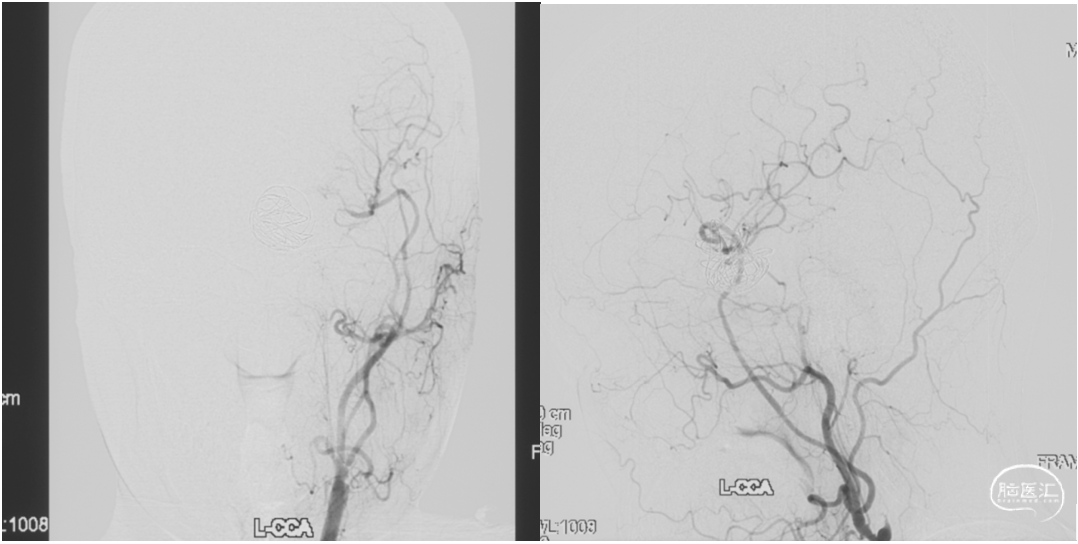

颈内动脉狭窄状况及闭塞试验

1. 术后一周复查DSA显示动脉瘤无血流,桥血管通畅。